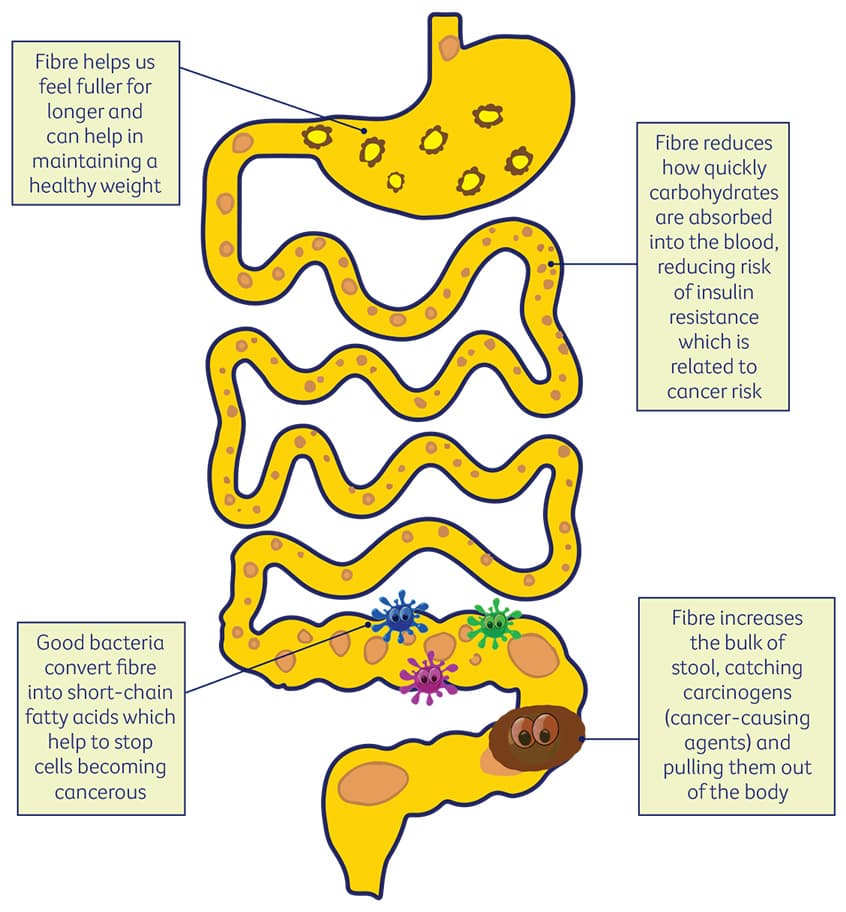

penile cancer photos download

Posts: penile cancer photos download